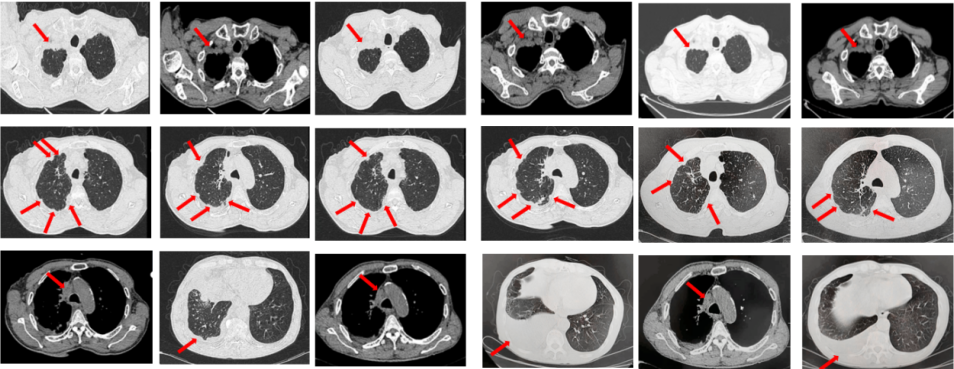

67岁女性患者,无既往病史。2019年10月患者因右侧季肋部不适行肺CT提示右肺中叶改变,双肺结节,右侧胸腔积液。行右侧胸腔穿刺引流,送检胸腔积液,液基薄层结果提示肺腺癌。确诊为右肺中叶恶性肿瘤cT2bN1M1a IVA期。基因检测(胸腔积液):EGFR L858R突变。建议患者口服奥希替尼,患者拒绝。2019年11月始口服埃克替尼,定期复查,最佳评效PR(图5)。

图5:A.第2例患者的基线影像资料,由上至下依次为右肺肿物、双肺转移灶及右侧胸腔积液;B.EGFR-TKI一线治疗后最佳复查评效,肺内病灶较前缩小,胸腔积液较前明显吸收。

2020年11月复查评效PD。复测基因检测(血检):T790M阳性,改行奥希替尼治疗,期间评效均为SD(图6)。

图6:A.埃克替尼靶向治疗后病情进展,肺内病灶较前增大,右肺近胸膜处新发转移灶;B.更换三代EGFR-TKI治疗后复查多处病灶未见明显变化。

如图7所示,2021年7月复查评效PD。重新行右肺穿刺取得病理,提示腺癌。NGS组织基因检测:MET基因扩增(变异倍数)4.0倍。改行赛沃替尼联合奥希替尼治疗。治疗10日后突发一过性寒战伴低血压,不除外药物相关,对症治疗后好转。复查评效达PR,因患者无法耐受药物不良反应,改行奥希替尼联合克唑替尼治疗至今,定期复查,最佳评效PR,末次评效SD(2024年7月)。

图7:A.奥希替尼治疗后病情进展,右肺内病灶较前再次增大,同时右肺内新发转移灶;B.出现MET扩增后,奥希替尼联合MET-TKI治疗后肺内病灶较前明显缩小;C.当前方案治疗持续有效。